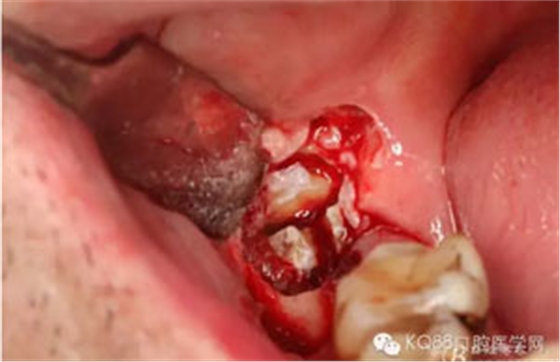

圖9.高速牙鉆分牙:

圖10.先頰舌向橫斷、然后再把牙冠近遠(yuǎn)中向縱分

圖11. “T”型的分牙。